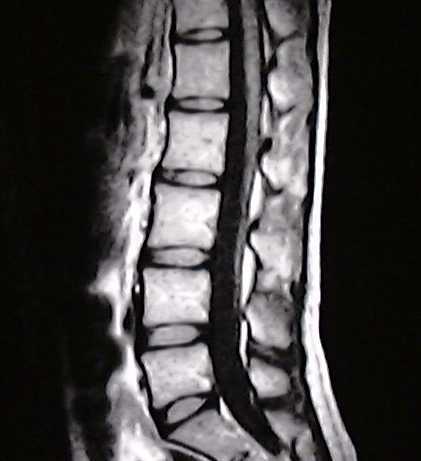

*google画像より引用

上の写真が椎間板ヘルニアの写真で、右の写真は正常な腰椎の写真です。

これを見るといかにも左の写真は痛そうに見えます。しかし、、、